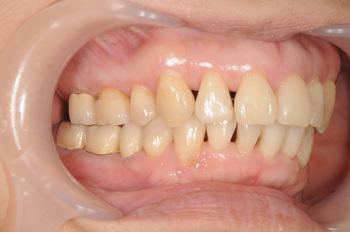

Before

インプラント治療は順調に進みましたが、咬み合せの治療に関しては時間を要します。欠損を招くような不正咬合は、咬合崩壊といって、咬み合わせが壊れてしまう状態が始まっていることもあります。まずはこの患者様の咬み合せにおいて、どこで噛み合うことが正しいのかを探しながら、ワイヤーの強制力でその位置に顎の歪み・ズレを元に戻す治療を行っていきました。

約2年間の矯正を経て咬み合せもしっかり合うようになりました。